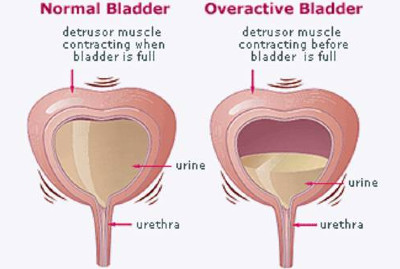

Υπάρχουν τέσσερα βασικά είδη ακράτειας

Πρόκειται για την ακούσια διαφυγή ούρων κατά την διάρκεια απλών δραστηριοτήτων, όπως ο βήχας, το γέλιο, το φτάρνισμα ή η σωματική άσκηση.

Είναι το συχνότερο είδος ακράτειας στις γυναίκες και οφείλεται στην χαλάρωση του πυελικού εδάφους (Εικ.1) αλλά και στην εμμηνόπαυση.